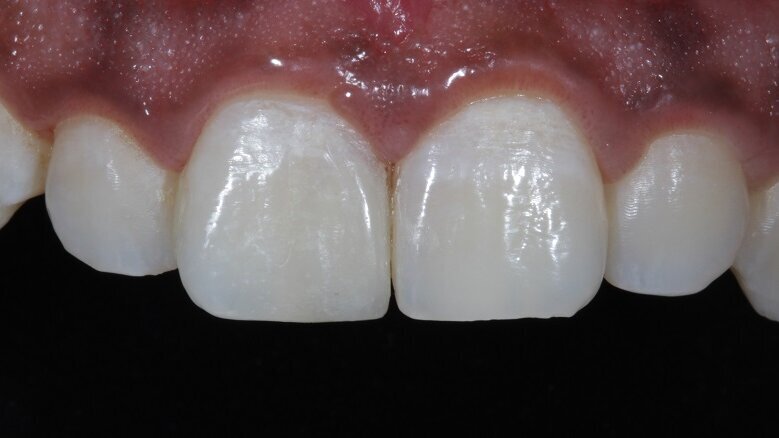

Fig 19: Symmetry achieved

Fig 21: Final Post-Operative photograph

Discs and rubber cups were used for the final polishing protocol. Bilateral symmetry was then achieved (Fig 19). A lateral view of the teeth depicted the surface texture (Fig 20). The patient was then recalled after 48 hours for a check-up (Fig 21).